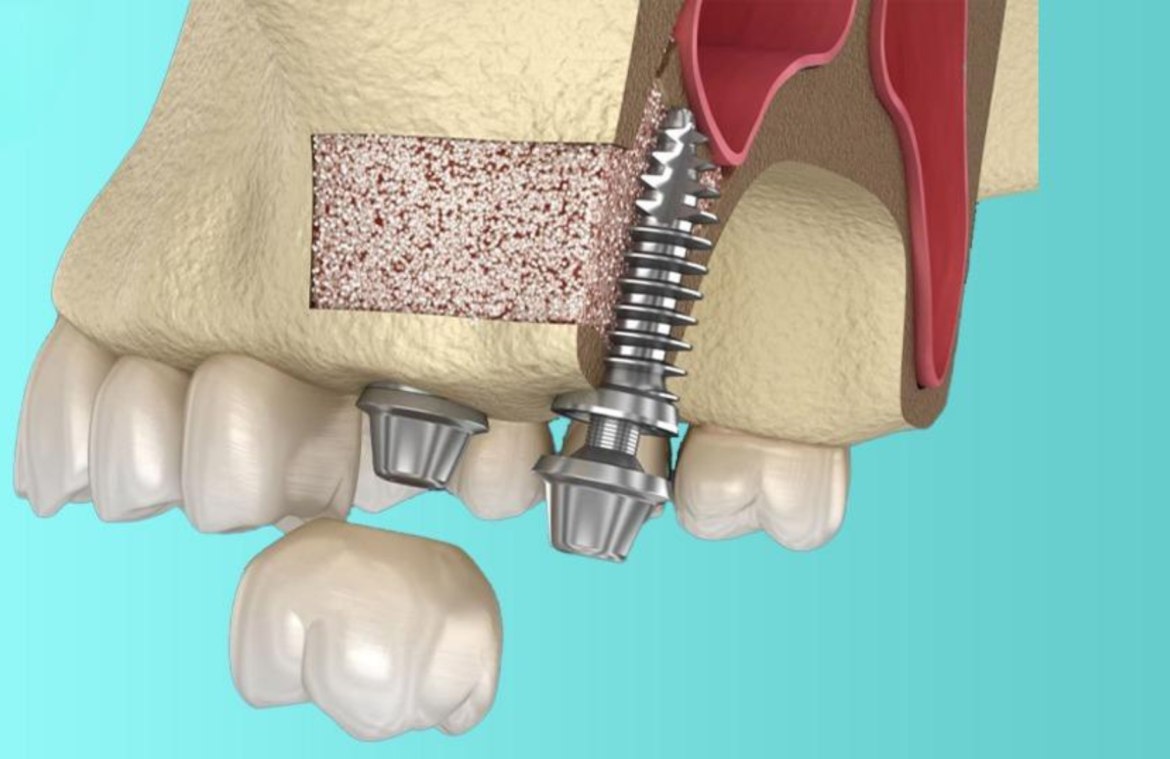

Nâng xoang hở làm dầy xương hàm trên

Trong một số trường hợp, khi cấy ghép Implant cần

Cấy ghép xương ổ sau nhổ răng, ghép xương

Ghép xương sau khi nhổ răng là phương pháp được